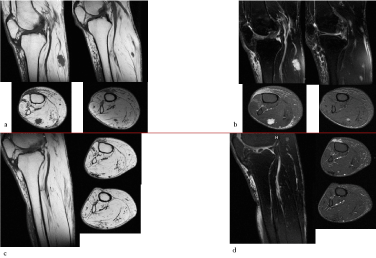

Magnetic Resonance Imaging scan (MRI) revealed, at the upper third of the calf at the level of the muscular belly of the lateral right twin, the presence of two expansive lesions, with polylobulates margins, one with diameters on the axial plane of 17x10mm and longitudinal extension of 20mm and the other with diameters on the axial plane of 5x6mm and longitudinal extension of 10mm. These formations were hyperintense in T2, hypointense in T1 and demostrated diffuse homogenous enhancement on post-contrast imaging. The findings described were in the first hypothesis compatible with expansive lesions of the nerve sheats (neurinomas, schwannomas), although plurifocality and irregular morfhology were not a typical sign (Figure 1).

Figure 1. The lesions appear hypointense in T1 weighted sequences (a), amd hyperintense in T2 weighted sequences (b), Post-operative MRI shows no recurrence at 11 months after surgery (c,d)